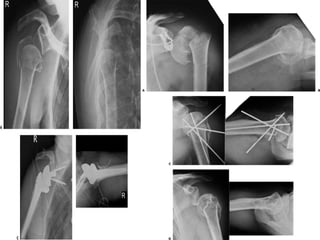

Tratamento cirúrgico  #3 partes(colo cirúrgico e grande ou pequena tuberosidade) - Na teoria os fragmentos são vascularizados, mas algumas vezes evolui c/ NAV(principalmente reduções cruentas, incruentas frustadas e idosos) - Redução incruenta difícil e instável - Desvio rotacionais depende do fragmento acometido

• 38.

- Melhores resultadosc/ amarilhas(simples,duplas, cerclagem ou combinadas) dos fragmentos ao redor pinos intramedulares c/ fio aço ou Ethibond(Sizinio)

Tratamento cirúrgico  Otratamento de escolha é a redução aberta com fixação estável independendo do tipo de material empregado. Quando não é possível a fixação, a artroplastia pode ser indicada  EFC 23 http://traumatologiaeortopedia.com/ http://ortopediabrasil.blogspot.com.br/

Tratamento cirúrgico  Hastede Hender modificada + amarrilha( 80% bom resultado- FMUSP-1997)  “para-quedas”(HSPSP) Amarillha intramedular ancorada parafusos(100% bom ou excelente resultado)  Lech e cols(26 2p, 11 3p e 1 4p) pino intramedular + amarrilha 34% excelente e 45% bons resultados

Tratamento cirúrgico  #4 partes são mais freqüentes em pacientes idosos com estrutura óssea fragilizada.  Impactada valgo e pouco desvio das tuberosidades pode tentar tt* conservador  A circulação está comprometida com índice de NAV ao redor de 25% dos casos.  São fraturas instáveis e de difícil fixação  Jovens deve-se tentar osteossíntese como primeira opção de tratamento, uma vez que existe uma melhor qualidade óssea  Idosos  prótese?????????